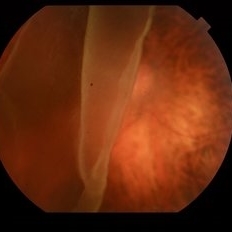

Choroidal Rupture

Jun 29 2013 by Jason S. Calhoun

Adult male with trauma to the right eye and orbital floor fracture. Hemorrhage with choroidal rupture.

Photographer: Jason S. Calhoun, Mayo Clinic Jacksonville, Florida

Imaging device: TOPCON TRC 50-EX

Condition/keywords: choroidal rupture